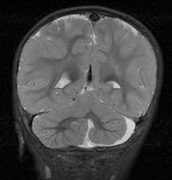

STURGE-WEBER SYNDROME Sturge (1879) reported the case of a child with facial “port-wine stain,” epilepsy, buphthalmos, and a dark choroid.204 Schirmer had noted the association of the facial vascular malformation and glaucoma in 1860.3 Weber (1922) reported brain X-ray findings of parallel streaks (“railtrack” sign), which he interpreted to represent calcific changes (Fig. 19).205

The PWS may not entirely respect the midline, possibly a reflection of transmedian innervation.212 The lesion grows proportionally with the child, often becoming darker in color. 213 The overlying skin may develop nodularity or hypertrophy in two-thirds of patients (by the fifth decade).214 Treatment with a pulsed-dye laser may significantly improve the appearance, but recurrence (i.e., redarkening) is possible.215,216 A deficit in the number of perivascular nerves in port-wine stains suggests that abnormal neural modulation of vascular flow may be involved in their pathogenesis.217 Intracranial leptomeningeal capillary vascular malformation (Figs. 21 and 22) is associated with seizures and contralateral neuromuscular weakness. Central nervous system involvement correlates highly with ipsilateral involvement of the V1 dermatome by a PWS.208,218